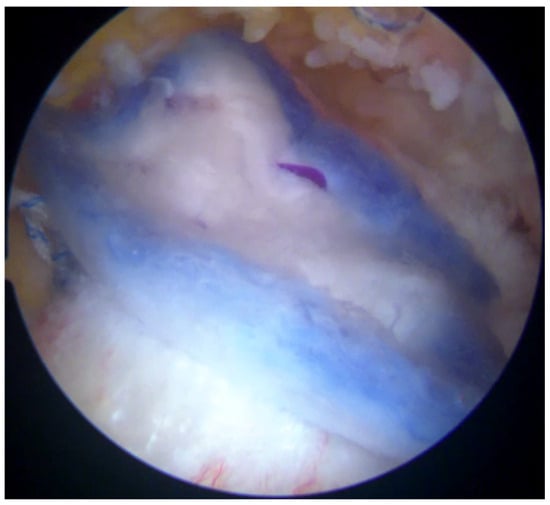

Post-repair arthroscopic visualization revealed a partial repair of the supraspinatus tendon, leaving a noticeable gap in the rotator cuff tissue (Figure 5).

Figure 5.

Rotator cuff repair has been achieved with two suture anchors, but a defect remained due to the absence of sheet 2 of the supraspinatus tendon.

To address this residual defect, a bioinductive collagen membrane (Regeneten, Smith and Nephew) was implanted to augment the repair and enhance healing. The Regeneten patch is available in two sizes, with the appropriate size selected based on the tear’s dimensions and morphology. The bursal surface of the patch is distinctively marked to differentiate it from the interlaced articular surface.

A thorough bursectomy was performed to create adequate space for patch augmentation. Soft tissue lateral to the tendon insertion was ablated to ensure direct contact between the lateral edge of the implant and the bone. The patch was loaded onto an arthroscopic delivery device and introduced into the subacromial space via a lateral cannula. After achieving the desired medial-to-lateral positioning over the repair construct, the delivery device was engaged, allowing the implant to unfurl. Two additional accessory portals were created for optimal anchor placement. Anchors were deployed with precision, using a quick motion to secure the implant to the tendon construct. Eight tendon anchors were inserted to affix the patch securely along its edges, ensuring stabilization (Figure 6). Although bone anchors could be used to enhance the contact between the lateral portion of the implant and the bone, they are not commonly utilized by the senior Author.

Figure 6.

The bioinductive implant (Regeneten) was positioned carefully over the repaired tendon site. The implant served as a scaffold to encourage the growth of new tendon-like tissue and enhance the strength of the repair.

The stability and positioning of the implant were confirmed with a probe. Following the verification of the repair, all instruments were removed, and the surgical wounds were closed in the standard fashion.